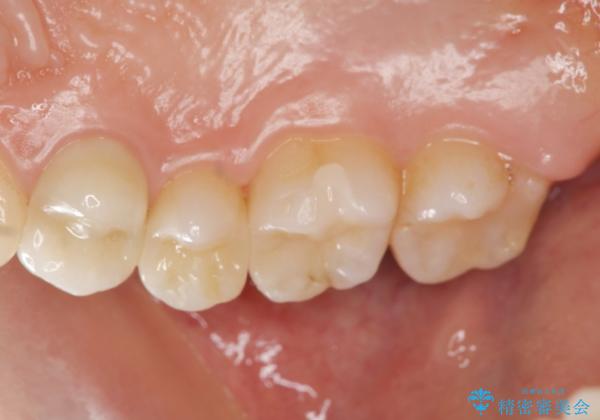

以前治療した歯が痛む 銀歯をセラミックに

- 歯が痛み、改善を求めて来院されました。

歯の神経の治療(根管治療)が必要であることをご説明し、同時に隣在する銀歯の除去も希望されたので同時に治療を行っていきます.

- 27万円(セラミックインレー×2 仮歯・ファイバーコア・ジルコニアクラウン)費用は治療当時の料金となります

虫歯治療は小さい場合にはセラミックインレー、大きな場合や痛みが生じている場合は根管治療ののちクラウンによる機能回復が必要となることが多いです。